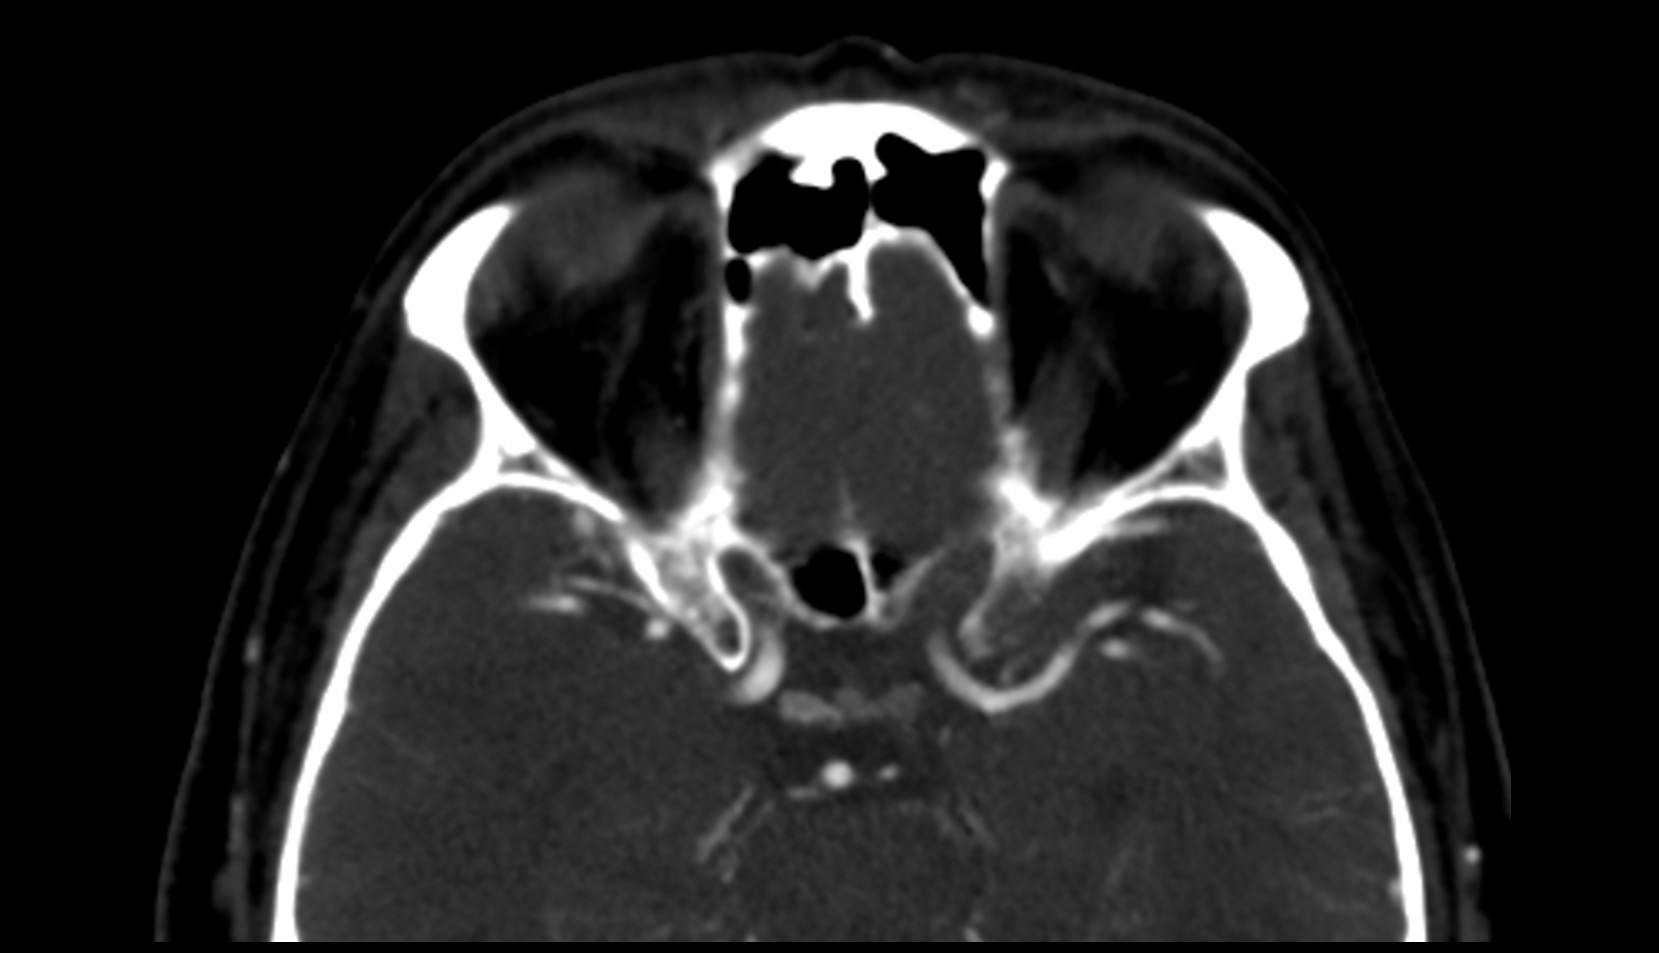

- Carotid cistern

- Chiasmatic cistern

- Optic chiasm

- Optic canal

- Intracanalicular part of optic nerve

- Jugular foramen